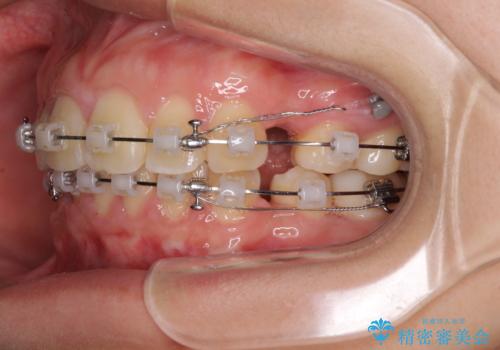

- クリアブラケット

- 2年5ヶ月

- 10-30回

- 上下前歯を部分矯正したところ出っ歯になってしまったとのことで来院された患者様です。

上下左右第一小臼歯4本を抜歯して、積極的に口元を引っ込めるよう、ワイヤー装置にて矯正治療を行うこととしました。